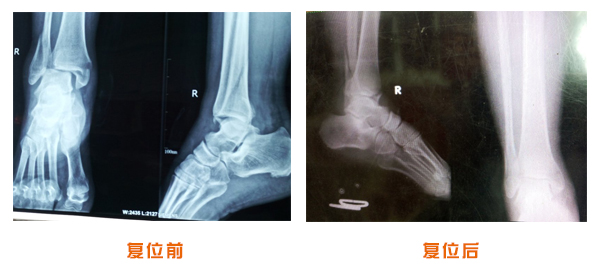

肥城市安駕莊梁氏骨科醫(yī)院是一所以梁氏手法正骨配合膏藥為特色的現(xiàn)代化??漆t(yī)院。

梁氏骨科術(shù)始創(chuàng)于清雍正年間,歷經(jīng)八代,至今已有三百年歷史。據(jù)1929年泰安縣志載“梁瑞圖先生,字增生,號蓮峰,安駕莊人,精岐黃并發(fā)明接骨,凡跌打車凡跌打車軋皮不破而碎骨者......【詳細(xì)】 |